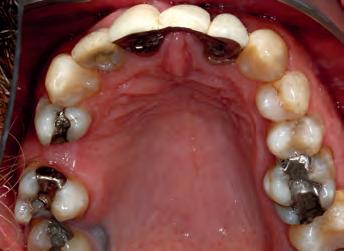

Patient: face before

A53 year old man attended complaining of pain from an existing bridge UR2 - UL2. It needed to be extracted because several roots were infected and would have required re-RCT, which the patient did not want to do. On closer inspection, the remaining teeth in the upper arch required some work as well (one RCT), but otherwise the teeth had a good prognosis.

The options were explained to the patient (implants, bridges/crowns/dentures) and the patient decided to save his remaining teeth. Written and verbal consent was obtained. We took clinical records and a series of DSLR photos and intraoral scanning with the Carestream 3600 intra oral scanner with scan flow software. The CS 3600 was chosen because of the comprehensive restorative features such as checking how much tooth structure has been removed compared to the pre-op tooth shape, as well as checking for any undercuts.

The decision was made, to extract the remaining upper incisors and make a temporary bridge from UR3 - UL3 in Luxatemp A3 with no immediate change to tooth shape or smile design.

TOP ROW: Before lower occlusal, Before retracted in occlusion 2ND ROW: Before retracted left in occlusion, Before retracted left open 3RD ROW: Before retracted open, Before retracted right in occlusion 4TH ROW: Before retracted right open, Before upper occlusal